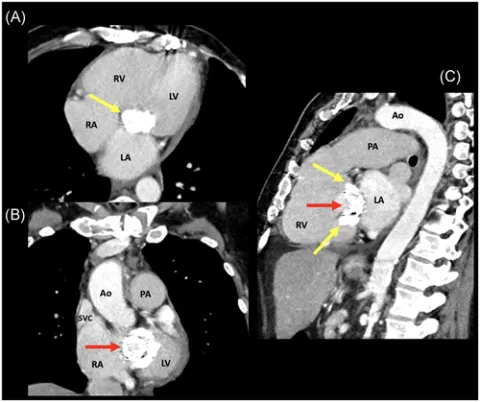

Transcatheter "valve-in-valve" mitral valve replacement for patient-prosthesis mismatch: Chronicle of a death foretold

Marin-Cuartas M, Noack T, Kiefer P, Borger MA. Transcatheter "valve-in-valve" mitral valve replacement for patient-prosthesis mismatch: Chronicle of a death foretold. J Card Surg. 2020 Dec;35(12):3606-3609. doi: 10.1111/jocs.15050. Epub 2020 Sep 28. PMID: 32985707.